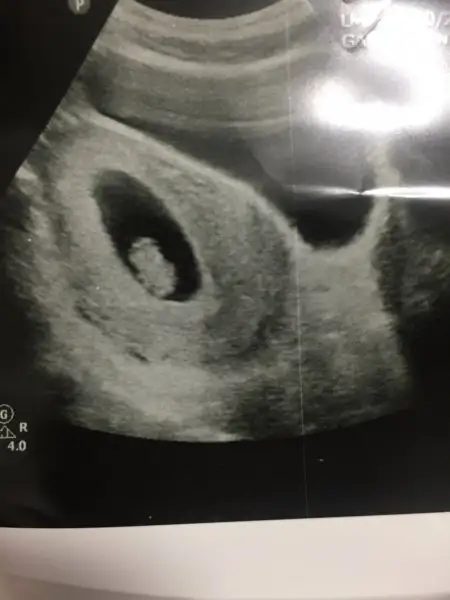

Teyzoslari bakin benim minik kurabiyem kocaman oldu bugun kontrolumuz vardi icimde kipir kipir hareket ediyordu cok duygulandim elimde olsa Sabah a kadar izlerdim onu ilk Hamilelik olunca acaip oluyorum farkli hissediyorum :emir_bebek::anneadayı:

• IMG_2162.webp

IMG_2162.webp

9,8 KB · Görüntüleme: 88